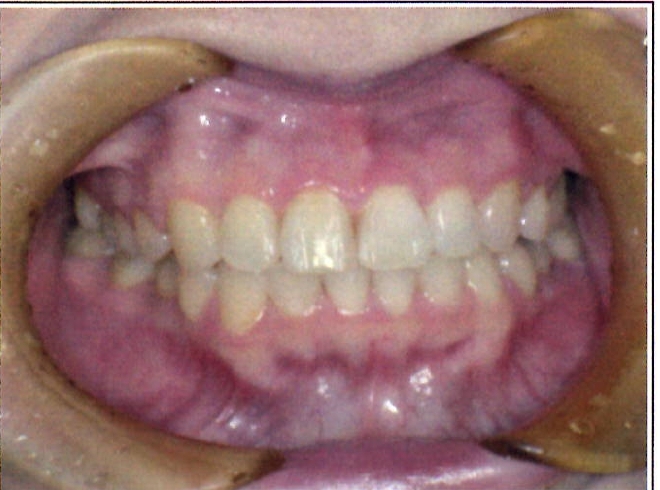

| 主訴・治療前の状態 | 著しい叢生(歯並びのガタガタ)があり、また6歳臼歯(第一大臼歯)が破折していた状態でした。 |

| 治療内容 | 通常の抜歯矯正では第一小臼歯(4番)を抜歯することが多く、その方が治療期間を短縮できますが、小川さんの場合は破折していた6歳臼歯を抜歯し、そのスペースを活用して歯列を整えました。これにより、健康な歯の本数を維持しながら矯正治療を行うことができました。 |

| 治療結果 | 治療前と比較して歯並びが大きく改善し、見た目も大幅に良くなりました。患者様にも大変喜んでいただけた症例です。 |